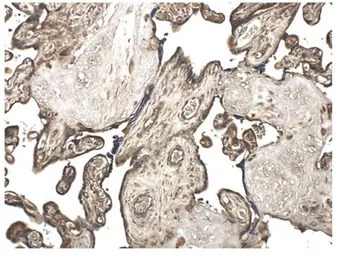

IHC-P analysis of formalin fixed human placenta tissue using GTX52477 MMP10 antibody [9G10].